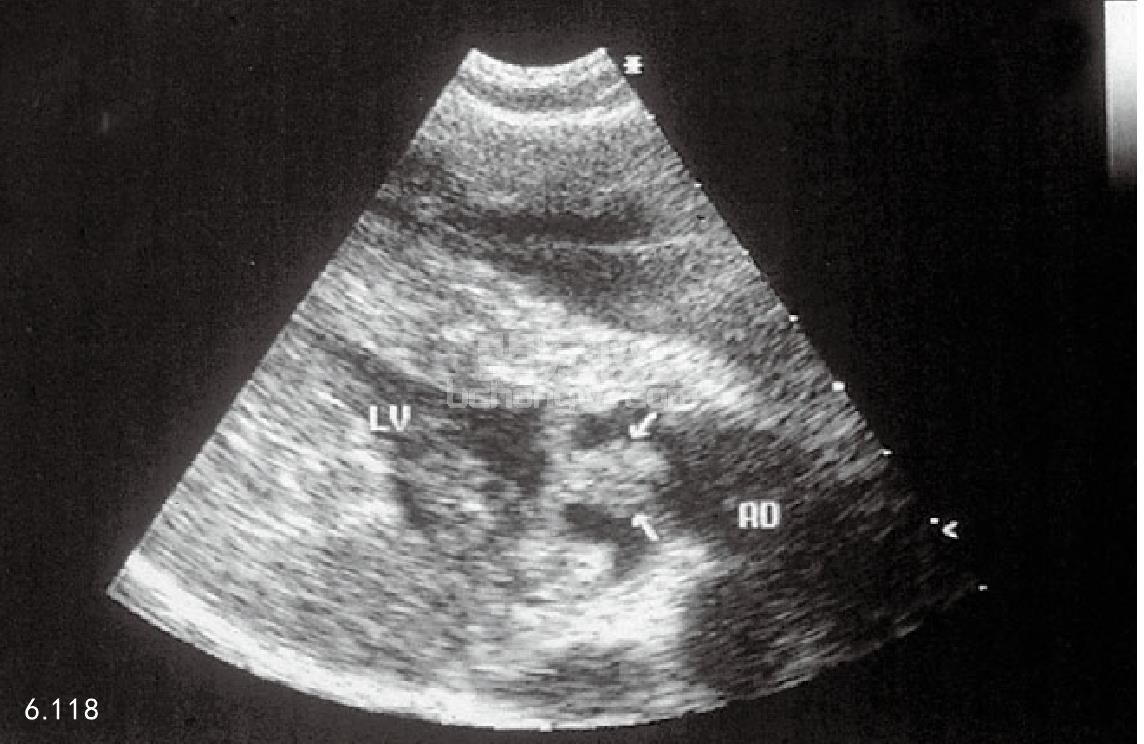

超声波心动描记术 对于细菌性心内膜炎的确诊,超声波心动描记术是最有效和可靠的技术(图6.118)。 可在心脏瓣膜和心内膜壁上看到一般大小的赘疣。

图6.118 为5岁拳师犬的超声波心动描记,其细菌性心内膜炎波及动脉瓣, 注意瓣膜增厚。